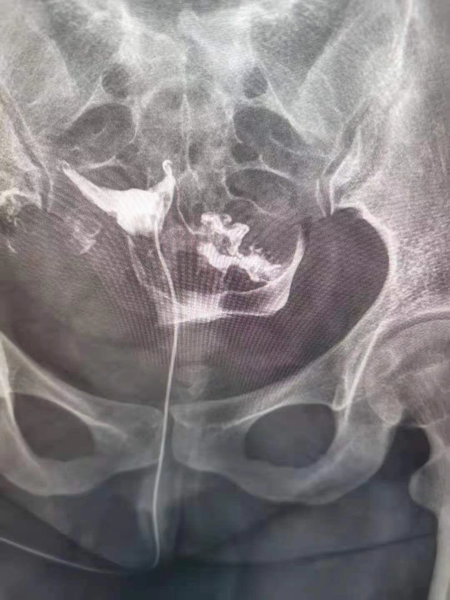

女性不孕中,子宮輸卵管因素導致的不孕約占50%,輸卵管在受孕的過程中具有重要地位,精子和卵子在輸卵管壺腹部相遇形成受精卵,然后依靠輸卵管的蠕動和管腔內纖毛的擺動將受精卵送回宮腔,而胚胎的著床、胎兒的孕育都是在子宮內完成。因此檢查子宮及輸卵管狀態是不孕癥診治的重要步驟。

1.造影成像的圖像質量清晰直觀,臨床醫生可以通過讀片來判斷子宮輸卵管腔內的狀態,清晰的圖片對于炎癥、積水等異常診斷更為準確,降低了漏診率和誤診率,對下一步不孕癥的處理方向提高幫助。

2.診斷同起到治療作用,輸卵管內的炎癥碎片、粘液栓、細小的纖維絲均可引起輸卵管的閉塞,并且輸卵管腔內有復雜的皺襞樣結構,造影劑在通過輸卵管腔時,可通過沖刷疏通的作用,改善輸卵管腔內的粘連堵塞,為精子和卵子的運送提供暢通的道路,還可以恢復腔內纖毛的活動,為運送受精卵做好準備。